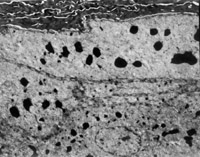

2. 電鏡觀察 受傷當(dāng)日上皮組織變性壞死,可見(jiàn)單核細(xì)胞核偏移、固縮,并有吞噬現(xiàn)象(圖5-3-12)。

5-3-12 燒傷當(dāng)日,單核細(xì)胞核偏移,固縮,并有吞噬現(xiàn)象  TE×8000